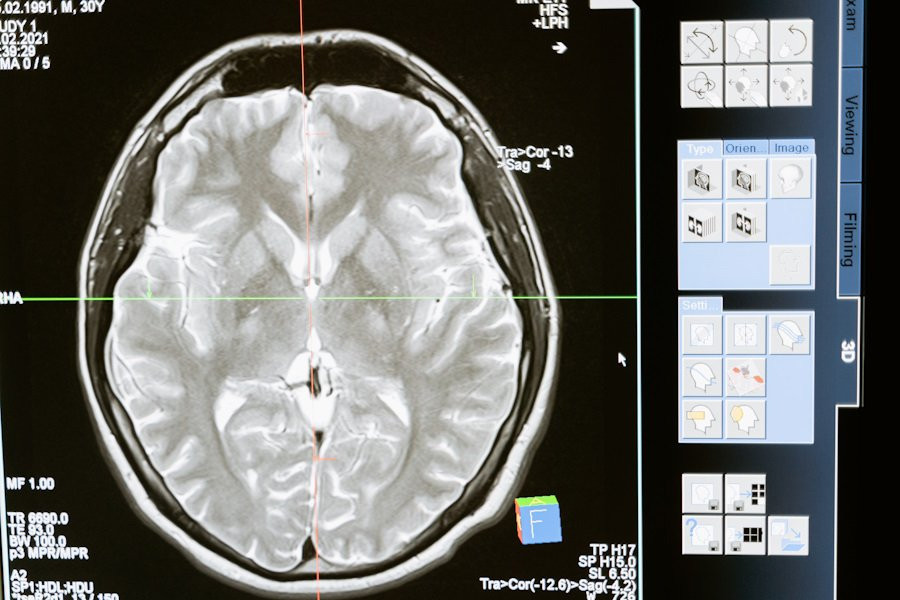

Учёные НИИ нейронаук СамГМУ разрабатывают инновационный подход к лечению болезни Паркинсона, опирающийся на использование метода транскраниальной магнитной стимуляции. В настоящее время основным методом лечения болезни Паркинсона является применение медикаментов, которые лишь замедляют прогрессирование болезни и смягчают ее симптомы. На текущий момент исследования продолжаются, сообщает RG.RU.

Транскраниальная магнитная стимуляция (TMS) - это метод медицинского исследования и терапии, который использует магнитные поля для воздействия на мозг человека. Этот метод немедленно и неинвазивно воздействует на активность мозга путем создания переменного магнитного поля над кожей головы.